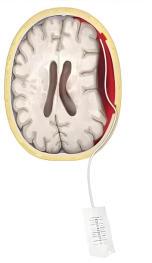

②手术治疗:出血量多,有神经功能障碍的应首选手术治疗,常常采用钻孔引流的手术方式,即在颅骨上钻一个小洞,使颅内的积血排出,并放置一根软管入颅内,留置1-3天使残留的积血持续排出。手术效果往往立竿见影,术后患者精神状态好转,思维变得清晰,乏力的肢体力量得到恢复等。但部分病人可能存在复发的可能,需定期复查;